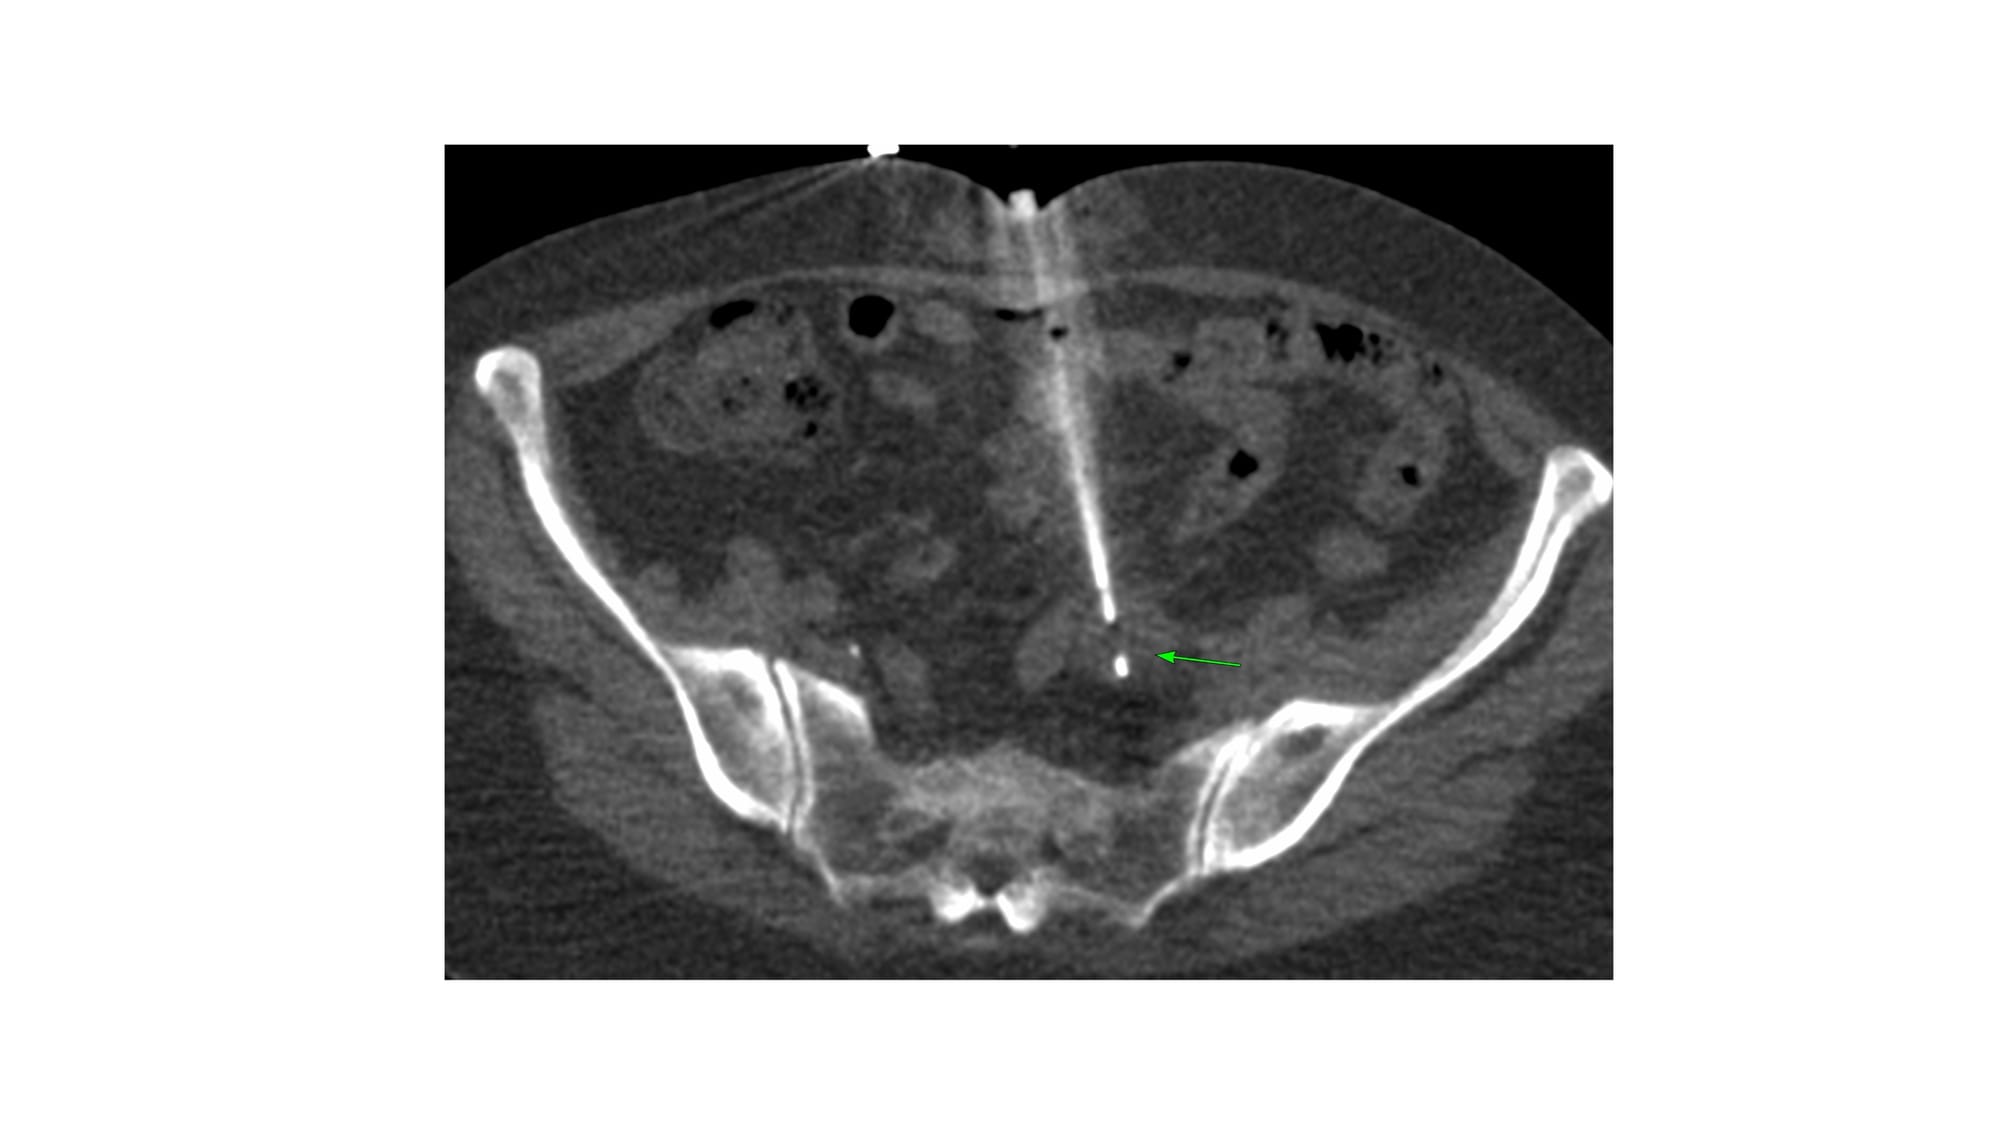

Case 164: Parting of the Bowel Loops with a Blunt-Tip

Bhavin Jankharia - 29 April 2025